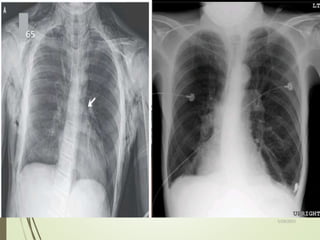

R

•Right lung more translucent than left

•Faint line just visible (zoomed view to follow)

•Pencil-thin white line

running parallel to chest

wall

•No lung markings lateral

to the line

Blade of right scapula

Right pneumothorax